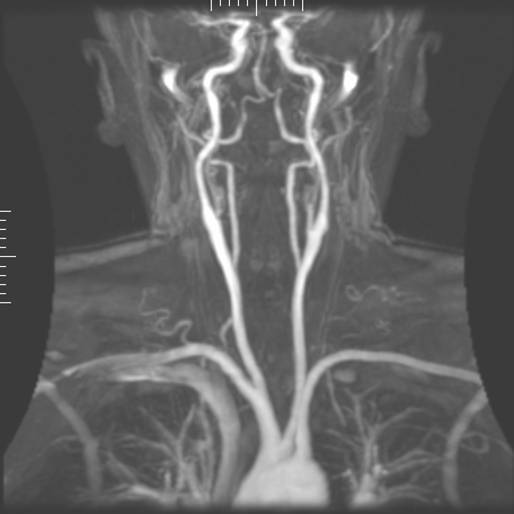

자기공명혈관조영술(MRA)은 협착(비정상적인 좁아짐) 또는 동맥류(파열 위험이 있는 혈관벽 확장)과 같은 동맥의 이상을 평가하는 데 사용되는 기술이다.[51] MRA는 목과 뇌의 동맥, 흉부 및 복부 대동맥, 신장 동맥, 다리 등을 평가하는 데 사용된다.[51]

MRA는 상자성 조영제(가돌리늄)를 사용하거나, "유속 관련 증강" 기술(예: 2D 및 3D 시간 비행 시퀀스, FLASH MRI 참조)을 이용하여 혈관 영상을 생성한다.[51] 유속 관련 증강은 영상의 대부분의 신호가 그 평면으로 최근에 이동한 혈액 때문인 현상을 이용한다. 위상 축적 기술(위상 대조 혈관조영술)을 사용하면 유속 속도 맵을 생성할 수 있다.[51] 자기공명정맥조영술(MRV)은 정맥을 영상화하는 유사한 방법으로, 조직을 하부에서 여기하고 신호를 여기 평면 바로 위에서 수집하여 최근에 여기된 평면에서 이동한 정맥혈을 영상화한다.[52]